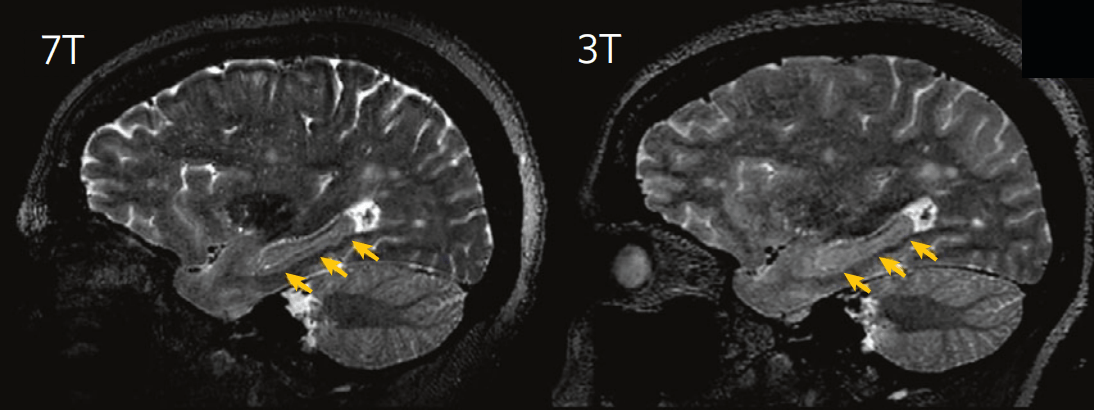

超高场弥散像数据预处理系统

该系统专为处理超高场强(如7T)磁共振采集的弥散像数据而设计。其核心算法专注于解决超高场数据中更显著的几何形变问题,提供高效的场图估计与形变校正流程。该预处理是确保后续所有弥散模型(包括DTI、DKI、NODDI等)分析结果空间准确性的关键步骤。